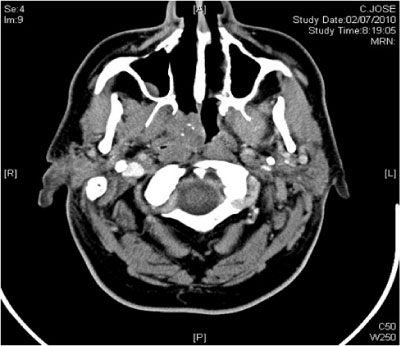

Computed Tomography demonstrated a right nasopharyngeal mass with slight contrasting uptake affecting the right nasopharynx without neck adenopathies (Figure 2).

Figure 2 Axial CT scan showing a Pleomorphic Adenoma affecting the right choana and the right nasopharynx without clear radiologic malignancy.